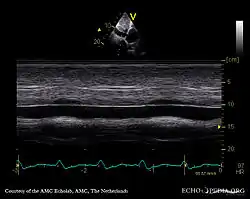

قصور الصمام ثلاثي الشرف أو قصور ثلاثي الشرف (بالإنجليزية: Tricuspid insufficiency) هو مرض يُصيب الصمام ثلاثي الشرفات، يُشير المرض إلى عدم إغلاق الصمام ثلاثي الشرفات بشكل كامل أثناء عملية الانقباض. يسمح هذا الخلل للدم بالتدفق إلى الخلف والحد من كفاءته.[2] يُمكن أن يكون سبب هذا القصور هو تغيير بنيوي لاحد مكونات الصمام ثلاثي الشرفات، من المُمكن أن تكون الآفة أولية (شذوذ داخلي المنشأ) أو ثانوي (توسع البطين الأيمن).[2]